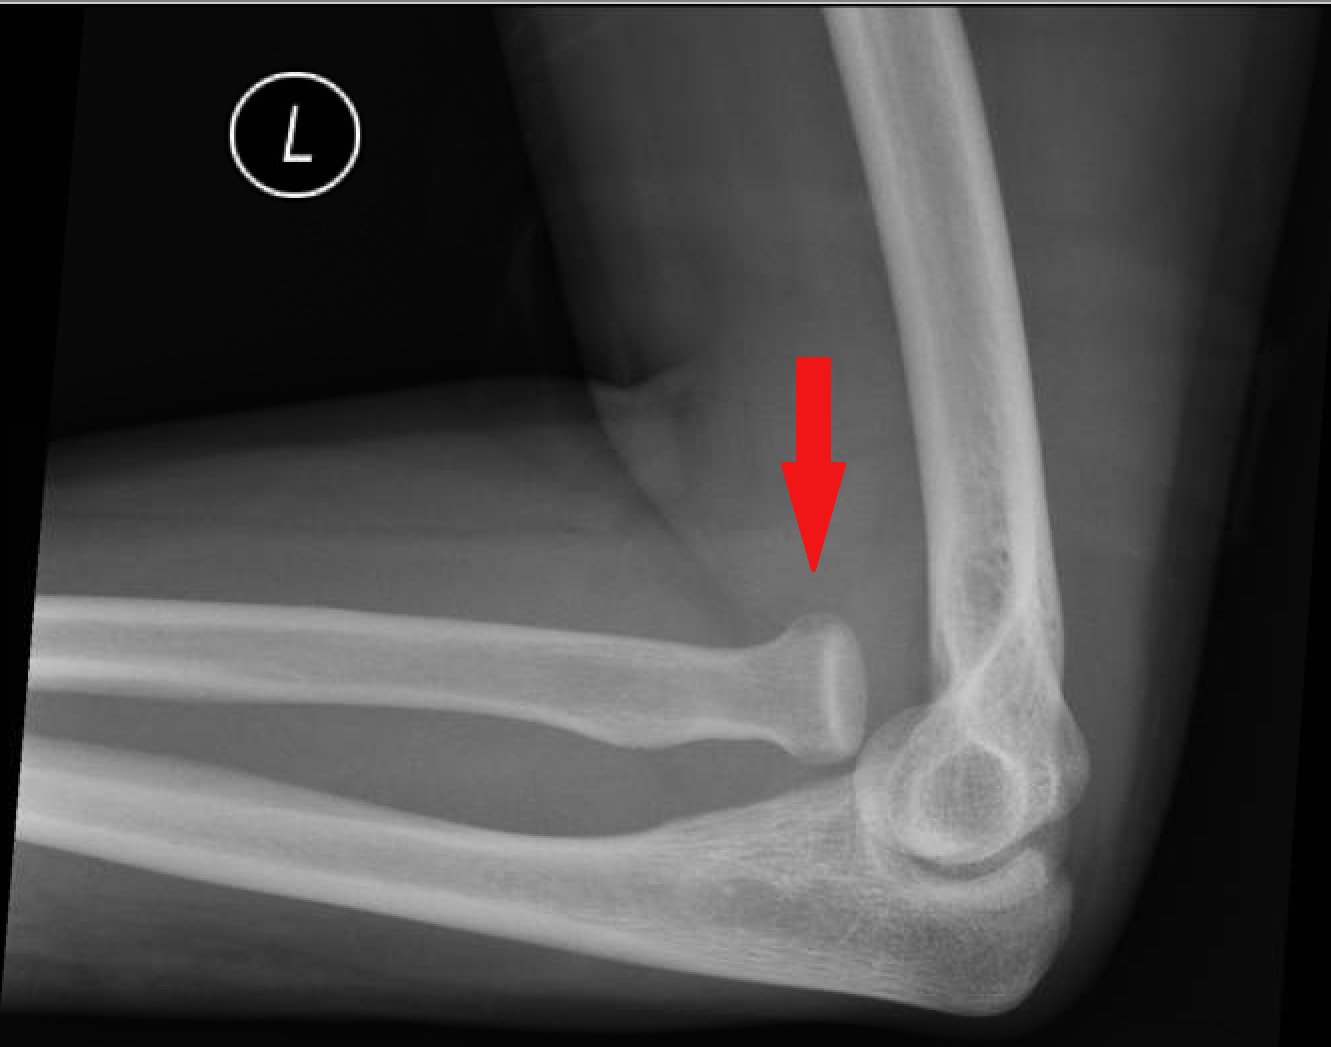

Monteggia fracture: It is defined as a fracture of the upper third of ulna with dislocation of the radial head.

Radiological features of Monteggia fracture:

1) Always suspect radial head dislocation with an isolated ulna fracture.

2) Carefully examine elbow views for normal alignment. A line drawn along the axis of the radius should pass through the centre of the capitellum on both the lateral and AP views. This is known as the radiocapitellar line.

3) The radiocapitellar line does not pass through thecapitellum due to radial head dislocational